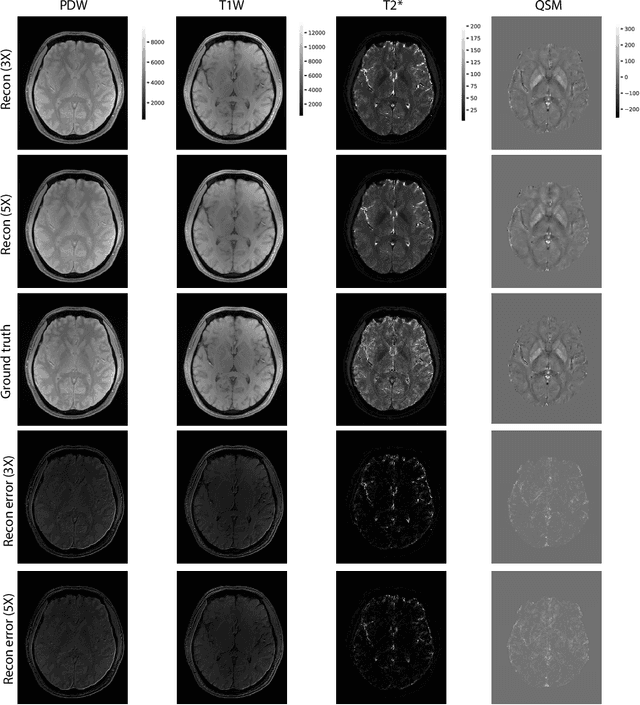

Abstract:Multi-contrast MRI images provide complementary contrast information about the characteristics of anatomical structures and are commonly used in clinical practice. Recently, a multi-flip-angle (FA) and multi-echo GRE method (MULTIPLEX MRI) has been developed to simultaneously acquire multiple parametric images with just one single scan. However, it poses two challenges for MULTIPLEX to be used in the 3D high-resolution setting: a relatively long scan time and the huge amount of 3D multi-contrast data for reconstruction. Currently, no DL based method has been proposed for 3D MULTIPLEX data reconstruction. We propose a deep learning framework for undersampled 3D MRI data reconstruction and apply it to MULTIPLEX MRI. The proposed deep learning method shows good performance in image quality and reconstruction time.